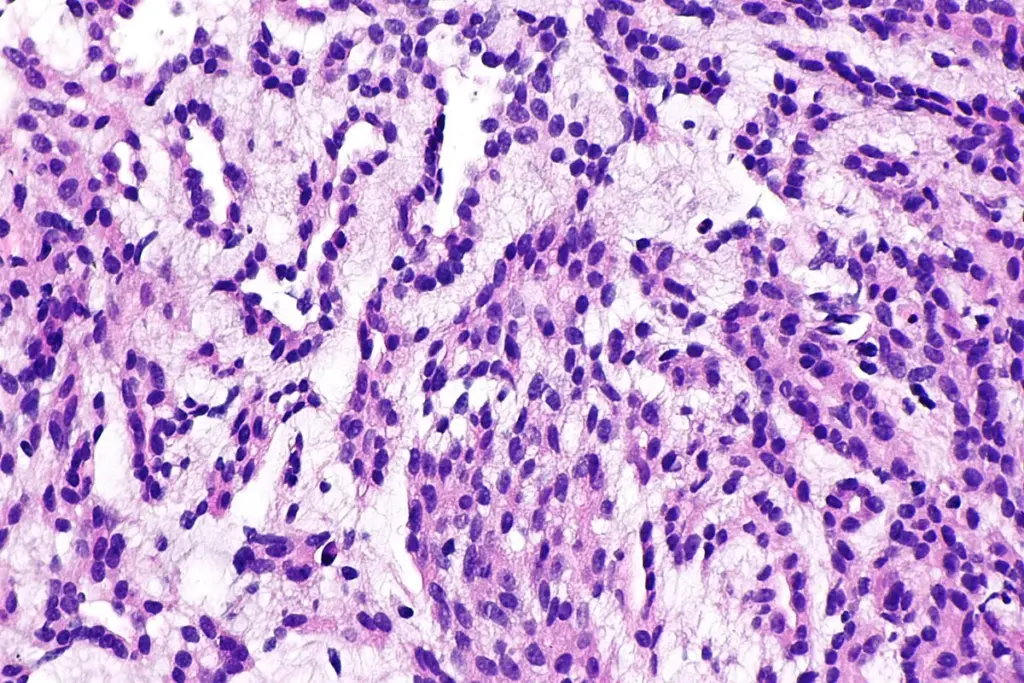

A precise cancer diagnosis is essential for creating an effective treatment plan. The process begins with a physical exam and a review of medical history. While imaging tests like CT scans, MRIs, and PET scans provide images of a tumor’s size and location, a biopsy is the definitive diagnostic tool. This involves removing a small tissue sample for a pathologist to examine. Blood tests may also be used to detect tumor markers. This collective data is then used to “stage” the cancer, a critical step that determines the extent of the disease.

When a symptom suggests cancer, a doctor will begin with a thorough physical exam and a review of medical history. If a specific area is suspected, the next step is typically an imaging test to visualize the inside of the body. However, cancer can only be confirmed with a biopsy. This procedure involves a specialist (such as a surgeon or radiologist) taking a sample of the suspicious tissue. A pathologist then analyzes these cells under a microscope to confirm the presence of cancer and identify its specific type.